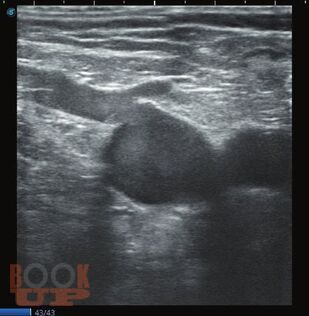

Ультразвуковое исследование вен нижних конечностей: анатомия, рефлюксы, тромбозы и хирургические подходы

Когда врач решает освоить ультразвуковое исследование вен нижних конечностей, первое, с чем он сталкивается - вен там очень много и в них легко запутаться. Кроме этого, в венах есть правильное направление течения крови, а есть неправильное - рефлюкс, и его нужно уметь правильно определять в нужных местах. Кроме рефлюксов, в венах встречается более опасное заболевание - тромбоз. Очень важно понять, где ситуация критическая и с найденным тромбом нужно срочно что-то делать, а где - ничего страшного, больному можно улыбнуться и сказать: «пройдет само». Кроме этого, в венах (в отличие от артерий) очень выражена индивидуальная изменчивость, нет понятия «нормальных» размеров и «гемодинамически значимого стеноза».